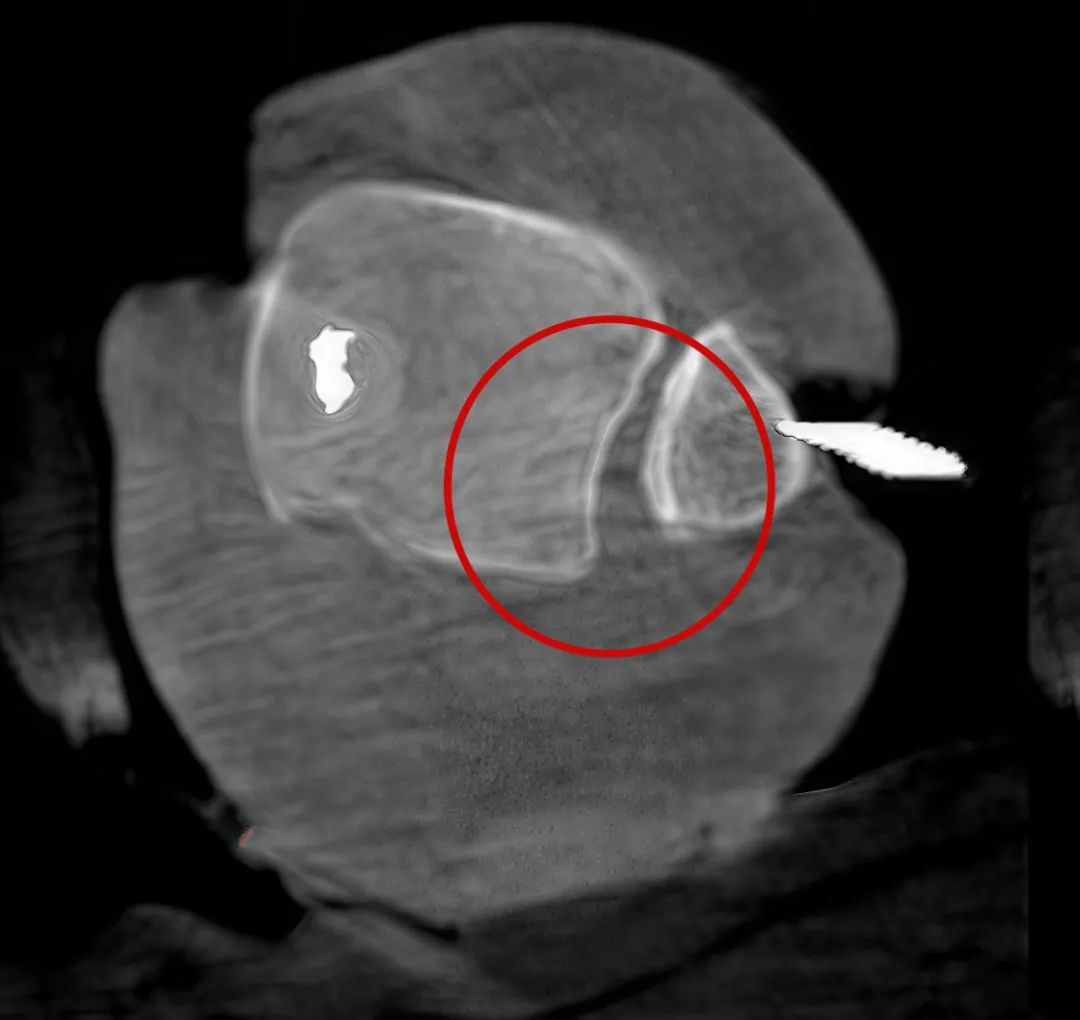

三維“類CT”影像

病例1:右側(cè)股骨遠(yuǎn)端骨骺骨病(13歲)

二維影像看不到病灶點(diǎn)

三維切面影像可以看出病灶點(diǎn)

二維C形臂提供的影像存在固有局限性,其成像原理是基于單一方位的投影,導(dǎo)致深部解剖結(jié)構(gòu)信息缺失,且容易受到骨骼和組織的重疊干擾,使得部分病灶難以清晰顯示,甚至被掩蓋。相比之下,三維C形臂通過三維重建技術(shù),可以獲得類似CT的斷層掃描圖像,從而解決了二維影像的重疊問題。